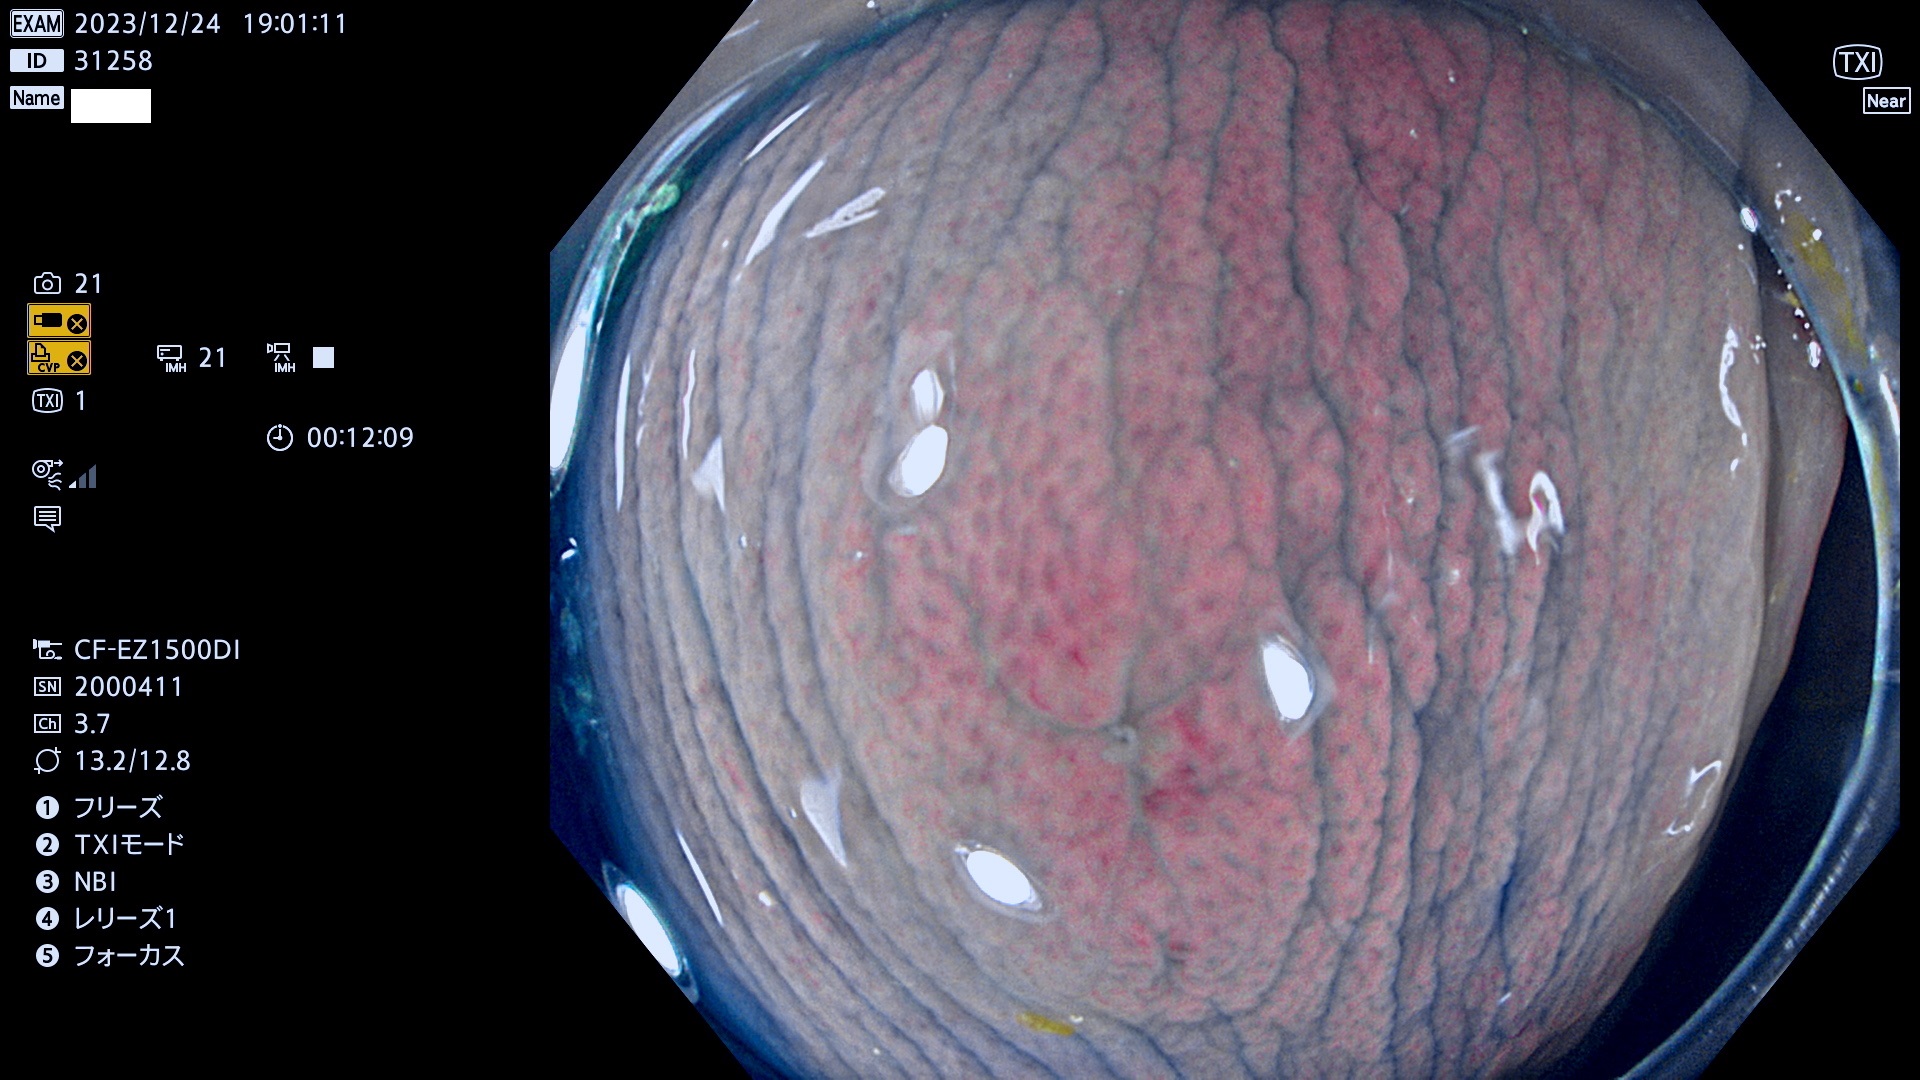

表面型腺腫(Flat Adenoma)の中で、完全に平坦な物をUb、陥凹している物をUcと呼びます。平坦隆起型(Ua)よりも、発見が難しく危険な病変です。

抽出の対象期間 2023年12月21日(木)〜12月24(日)の4日間(48件の検査)6件

当院で見つかった、炎症(ビラン)と極めて紛らわしい腺腫の例